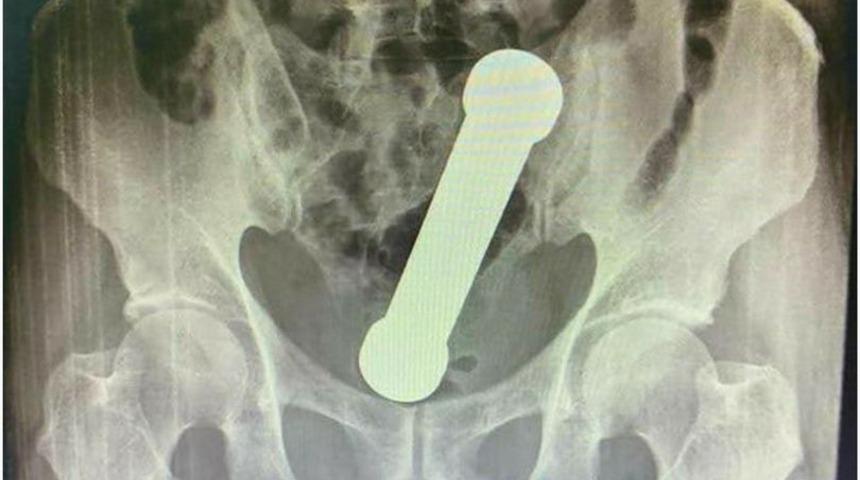

Muayene esnasında belli olmayan durum, hastanın röntgen filmi çekilince ortaya çıktı. Brezilya’nın Manaus kentinde yaşanan olayda sağlık görevlileri, cımbız kullanarak nesneyi dışarı çıkarmaya çalıştılar ancak başarısız oldular. Sonrasında daha acımasız bir yönteme başvurdular ve elle çıkarmayı denediler.